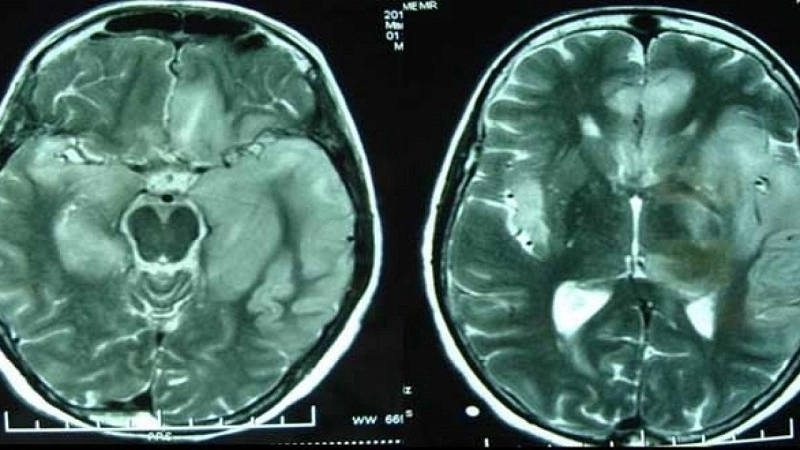

Image description of viral meningitis

Viral meningitis is an inflammation of the membranes surrounding the brain and spinal cord caused by viral infection. It is generally less severe than bacterial meningitis but can still cause serious symptoms such as headache, fever, and neck stiffness. Prompt recognition and preventive measures are crucial for reducing health risks.